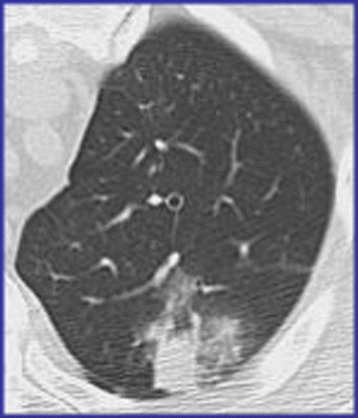

Patients with prolonged (>5 days) neutropenia are particularly susceptible to fungal infection (aspergillus, candida etc.) and antifungal therapy is associated with significant toxicity. Therefore, it is advocated to perform chest CT even in the presence of a normal chest radiograph, particularly if empirical antibacterial therapy does not result in a resolution of the symptoms (Fig. 4).

Therefore, in patients with suspected PCP chest CT may be helpful to demonstrate the typical pattern of ground glass opacity sparing the lung periphery with no associated lymphadenopathy or pleural effusion (Fig. 6).